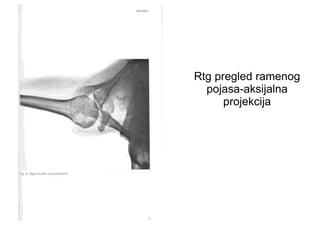

Rtg pregled ramenog

pojasa-aksijalna

projekcija